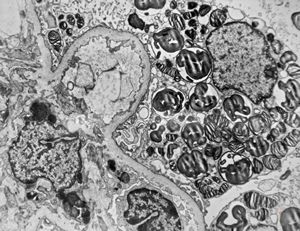

M,27y. | sea-blue histiocyte syndrome